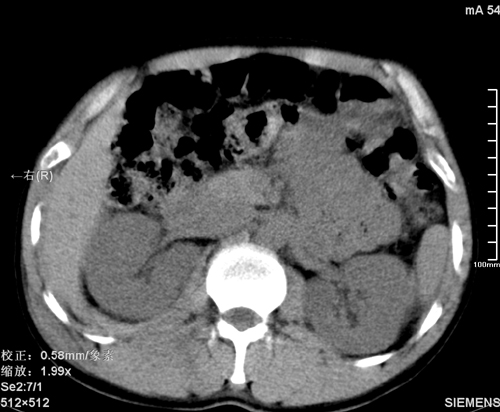

以下是引用qiushi在2008-3-28 12:00:00的发言:[br]腹膜后血肿,所见腰椎横突骨折.[br]建议上传骨窗、腰椎扫描.

以下是引用tao772在2008-3-28 12:29:00的发言:[br]右侧腹膜后积血,右侧腰大肌挫伤,右侧部分横突骨折. 肾脏最好报一下挫伤,必要时增强。